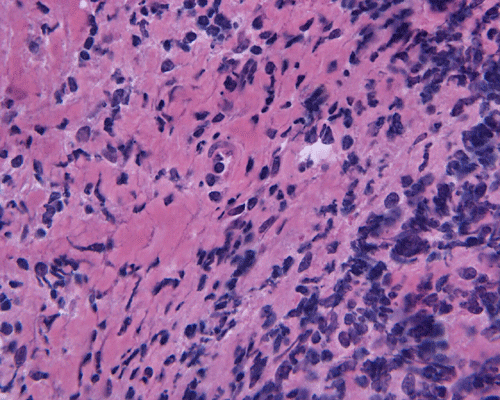

Pathology:

Intraoperative consultation: The specimen is that of a streotactic biopsy and is very small. The intraoperative cytologic preparation was rather hypocellular. Small clusters of cells with bland nuclei and foamy cytoplasm are present and they are highly suggestive of foamy histiocytes (Panel C). On frozen section, there are many small lymphocytes in a "pink" background that can be a granulomatous process (Panel D). In some areas, many foamy macrophages are present and one particular fragment appear to be a possible portion of a wall of structure with lining cells suggestive of macrophages (Panel E).

Paraffin sections: The entire volume of the tissue is made up of a granulomatous inflammation with poorly formed granuloma (Panel F, G, and H). The density of the lymphocytes is variable in different areas. In some areas, there is a rather intense lymphocytic infiltration accompanied by scant atypical cells with enlarged nulcei and prominent nucleoli (arrows in Panel I and J, Panel J is a higher magnification of Panel I). These atypical cells are quite easy to be missed. No microorganisms were identified by acid fast stain, PAS stain or GMS stain. The lymphocytes but not the atypical cells are positive for CD20 (Panel K) or CD3 (Panel L). The granulomatous background is strongly positive for CD68 (Panel M). Only rather faint positive staining for placental alkaline phosphatase (PLAP) is demonstrated and the interpretation is difficult as they are present in areas with crush artifact (Panel N). Many of the large, atypical cells are positive for CD117 (c-kit) (Panel O).

Intracranial germinoma is histologically identical to ovarian dysgerminoma and testicular seminoma. There is a tendency to infiltrate adjacent structures and to spread throughout the ependyma, the ventricular system and subarachnoid spaces. Microscopically, they consist of nests, lobules, cords, and/or sheets of large round tumor cells with well-defined borders, clear to pale cytoplasm with artifactual vacuolization, round and centrally located nuclei with open chromatin and prominent round or bar-shaped nucleoli. The cytoplasm is glycogen-rich, making these cells periodic acid-Schiff (PAS)–positive and diastase sensitive. These tumor cells are mitotically active. Atypical mitosis, however, is not a common finding. Necrosis is usually not prominent.  In the most classic histologic picture, clusters and cords of large germinoma cells are separated by a dense, lymphocytic infiltration admixed with some macrophages and a delicate fibrovascular network. Plasma cells may be found. At medium-power magnification with hematoxylin and eosin stain, the contrast between the smaller, darkly staining lymphocytes and the larger, pale staining cytoplasm of neoplastic cells is virtually pathognomonic. The amount of inflammatory cells can have wide variations among different tumors. In some occasions, the large germinoma cells are difficult to be found and the overall picture may suggest a lymphoma. Syncytiotrophoblastic cells can also be present. These cells should not be mistaken as evidence of choriocarcarcinoma.

Germinomas can elicit an atypical gliosis in the surrounding glial tissue which may be confused with malignant glial neoplasms. This is true particularly of specimens taken from the periphery of the germinoma. The tumor may appear as a desmoplastic tumor. The inflammatory response may be problematic in reaching a histologic diagnosis, especially in small biopsies, as macrophages can be difficult to distinguish from a non-seminomatous neoplastic component.

Granulomatous changes are common findings in germinomas and intracranial germinomas follow this general trend 3, 4, 5. It can be extensive. This feature is particularly problematic in neuropathologic when stereotactic biopsy is performed and the amount of tissue available for examination is limited as illustrated in this case. During intraoperative consultations, a frozen section diagnosis of granulomatous inflammation should prompt additional sampling as isolated granulomatous inflammation of infectious origin and sarcodosis are quite uncommon in the pineal gland.